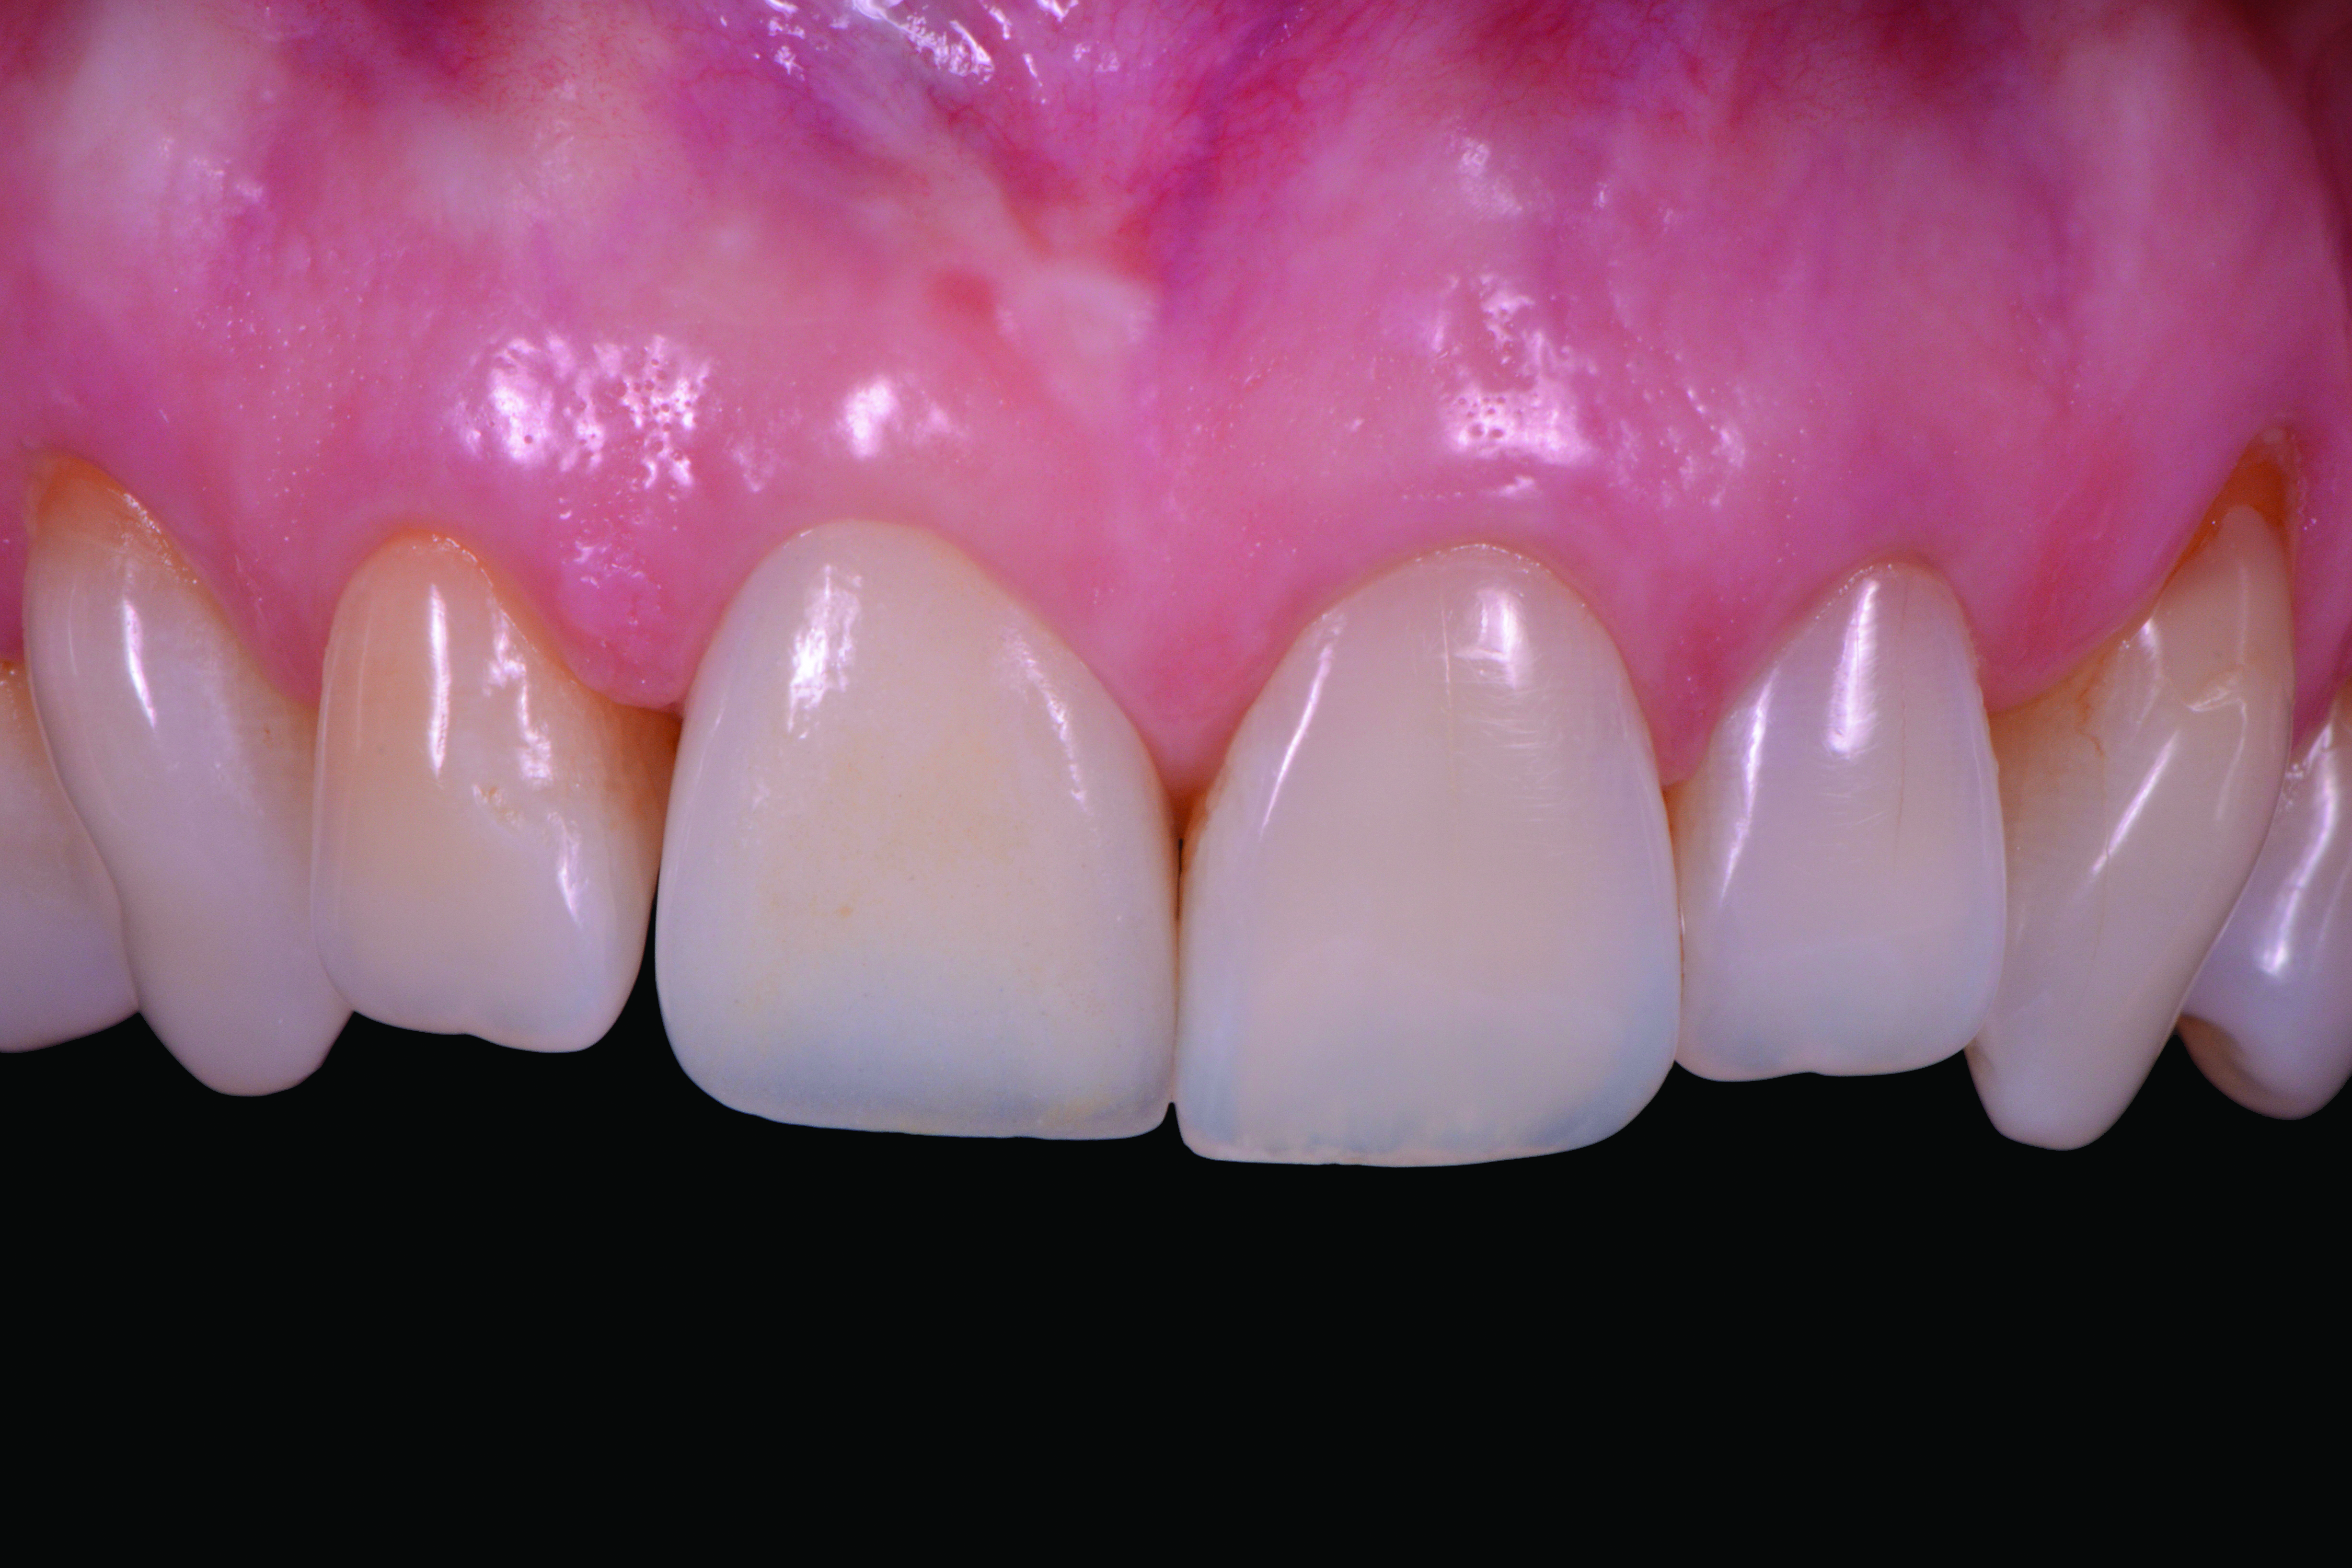

Fig 2. Frontal pre-operative view demonstrating acceptable mucosal esthetics.

Figure 2

Fig 9. Three-year recall of ATLANTIS Crown Abutment, demonstrating excellent soft-tissue stability and health.

Figure 9